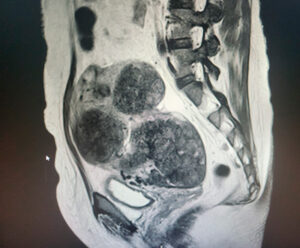

A 48-year-old woman presented with abdominal pain, fever (40.3 °C), nausea, and vomiting three days after undergoing hysteroscopic transcervical resection of a submucosal fibroid. Laboratory investigations showed a white cell count of 16.2 × 10⁹/L, neutrophils 13.9 × 10⁹/L, hemoglobin 102 g/L, and C-reactive protein 83 mg/L. She was started on intravenous co-amoxiclav and amikacin.

CT imaging demonstrated right hydrosalpinx with bilateral ovarian cysts (Figure 1), while MRI confirmed bilateral tubo-ovarian complexes (Figure 2). She underwent laparoscopic drainage of the abscess, adhesiolysis, and pelvic washout, with an estimated blood loss of 800 mL. Blood cultures grew ESBL-producing Escherichia coli, and antibiotics were escalated to intravenous meropenem. She was discharged after eight days on oral ciprofloxacin and metronidazole to complete a 10-day course.